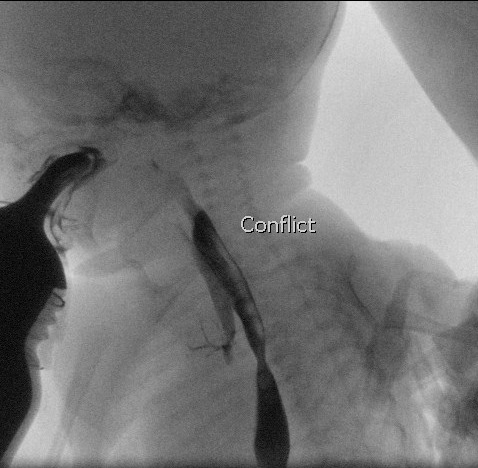

Se observa contraste saliendo del esófago hacia la tráquea a través de una fístula en N